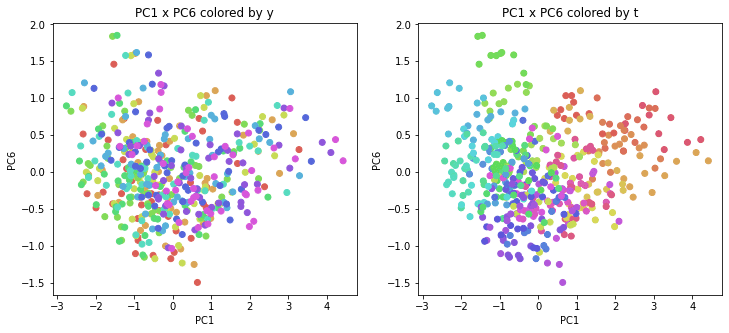

PCAの結果の第n主成分をPCnと表記します。

医療費データの場合と同様に、PCAの結果を見やすく表示するため、seabornのカラーパレットを使って、年月別、都道府県別に色分けして図示してみます(左側が年月別に色分け、右側が都道府県別に色分け)。PC1~PC8まで表示しました。

医療費データの場合ほどはっきりとはしていませんが、PC2が概ね時間の経過を表す成分で、残りの成分が時点によって変わらない地域の特徴を表す成分となっているようです。

また、PC1×PC3を見ると、47沖縄が他の都道府県からかなり離れたところに位置しており、沖縄の地域差が際立っているのが分かります。これは、以前別の記事で年齢階級のない健診データでPCAを実行した場合と似た結果となっています。

今回は、医療費データと同様に、健診データ240次元についてPCAを実行してみました。PCAの結果、医療費データの場合ほどはっきりしとはしていませんが、第2主成分が概ね時間の経過を表す成分で、時間軸に沿った全体的な動き(全国的な動き)を表しており、それ以外の成分が地域の特徴を表す成分で、この10年間あまり変わっていないことがわかりました。